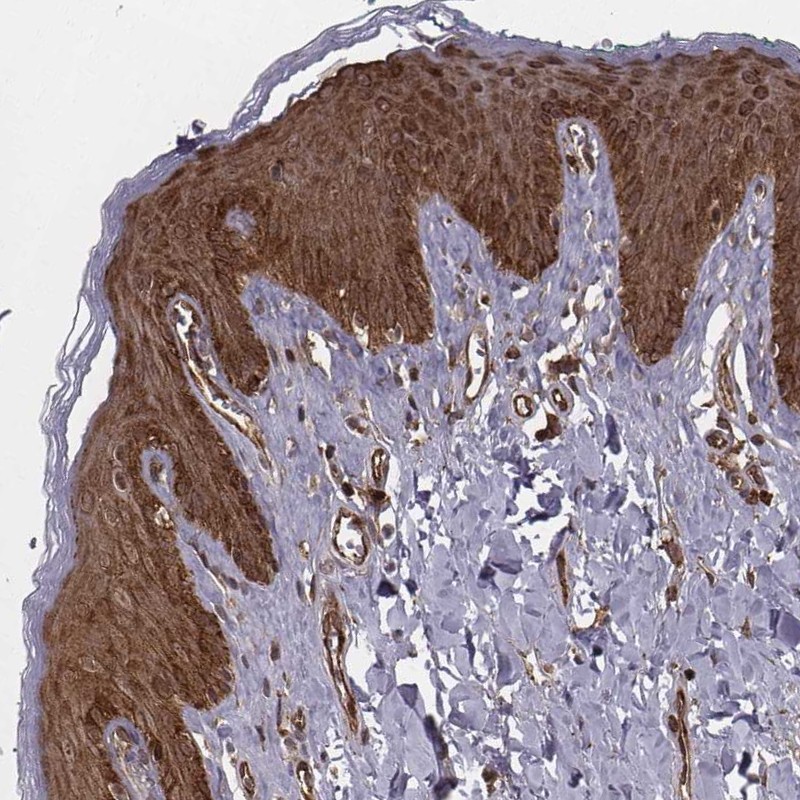

Immunohistochemical staining of human skin shows strong cytoplasmic and nuclear positivity in epidermal cells.